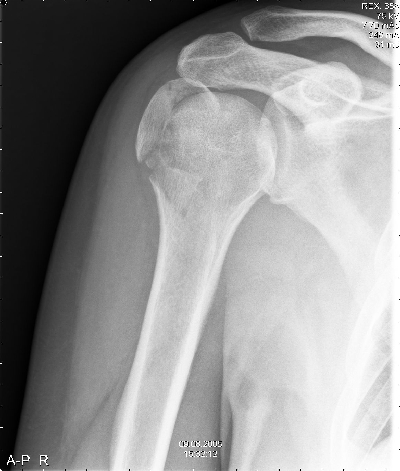

Na de ongelukige val was de arm uit de kom. |

|

Nadat deze was terug gezet zag het er weer goed uit. |